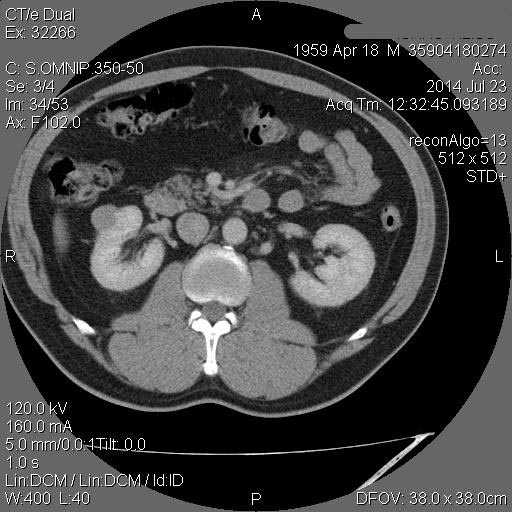

Рак - на первом месте. Показано КТ с контрастирванием.

Ответ каунасских радиологов - киста почки.

Пока оставляю случай на контроле.

В том то и дело. Но тем не менее - это киста, анамнез уже несколько лет.besliu писал(а):Что-то на узи на кисту не похоже...